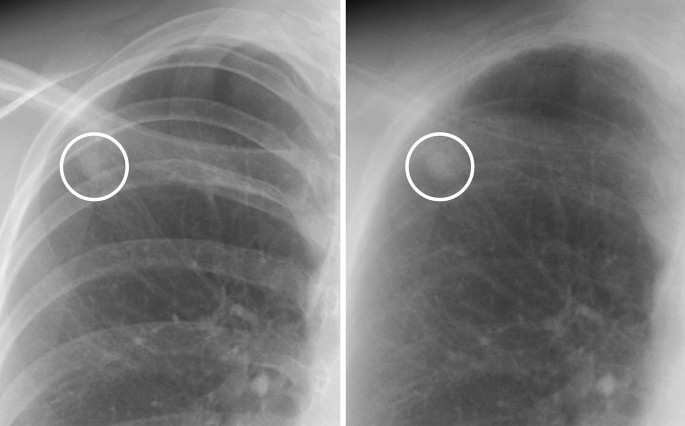

Representative images of nodules that were correctly diagnosed using soft tissue images are shown in Figs. 1, 2, 3 and 4.

A case of a calcified nodule not overlapping with the bone. (left) On the standard image, the evaluation of the presence or absence of calcification among readers was not consistent (confidence level of each reader: 1, 3, 2, 3 and 2, respectively). (right) In the soft tissue image, the nodule disappeared. All readers correctly evaluated it as calcified (confidence level of each reader: 1, 1, 2, 1 and 2, respectively).